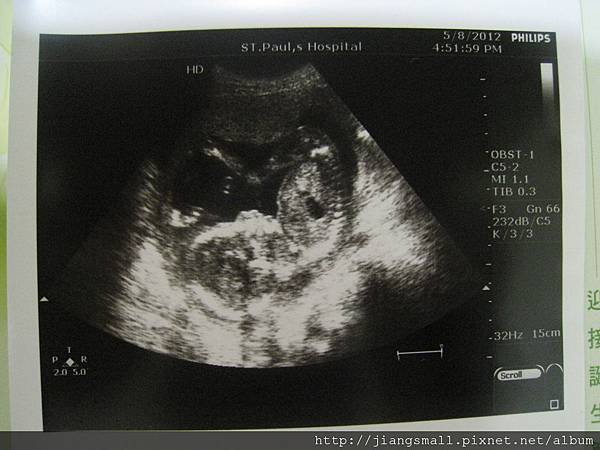

今天回去看初唐的報告,順利過關了。

也順便看看BB,在肚子裡動來動去了,難怪我肚子都會緊緊的。

照超音波時,醫生也是解釋了很多,可以說是高層次超音波的內容….。真不錯,每次都檢查很仔細。

照超音波時,在裡面吹泡泡…=..= 很悠哉嘛~~~